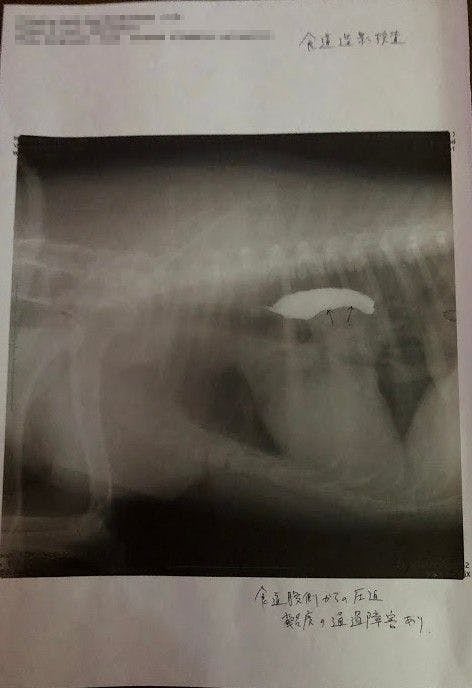

↑

バリウム飲んで検査してもらったところ、矢印の部分に腫瘍があり(白い部分は食道)、それが食道を押し上げているため、飲んだ水を吐いたりするとのことでした。(この時点で5センチほどの大きさの腫瘍でした。)

↑腫瘍の場所が体の奥のにある為、CT検査できる大学病院で検査してから手術するかどうか決めたほうがいいと言われました。